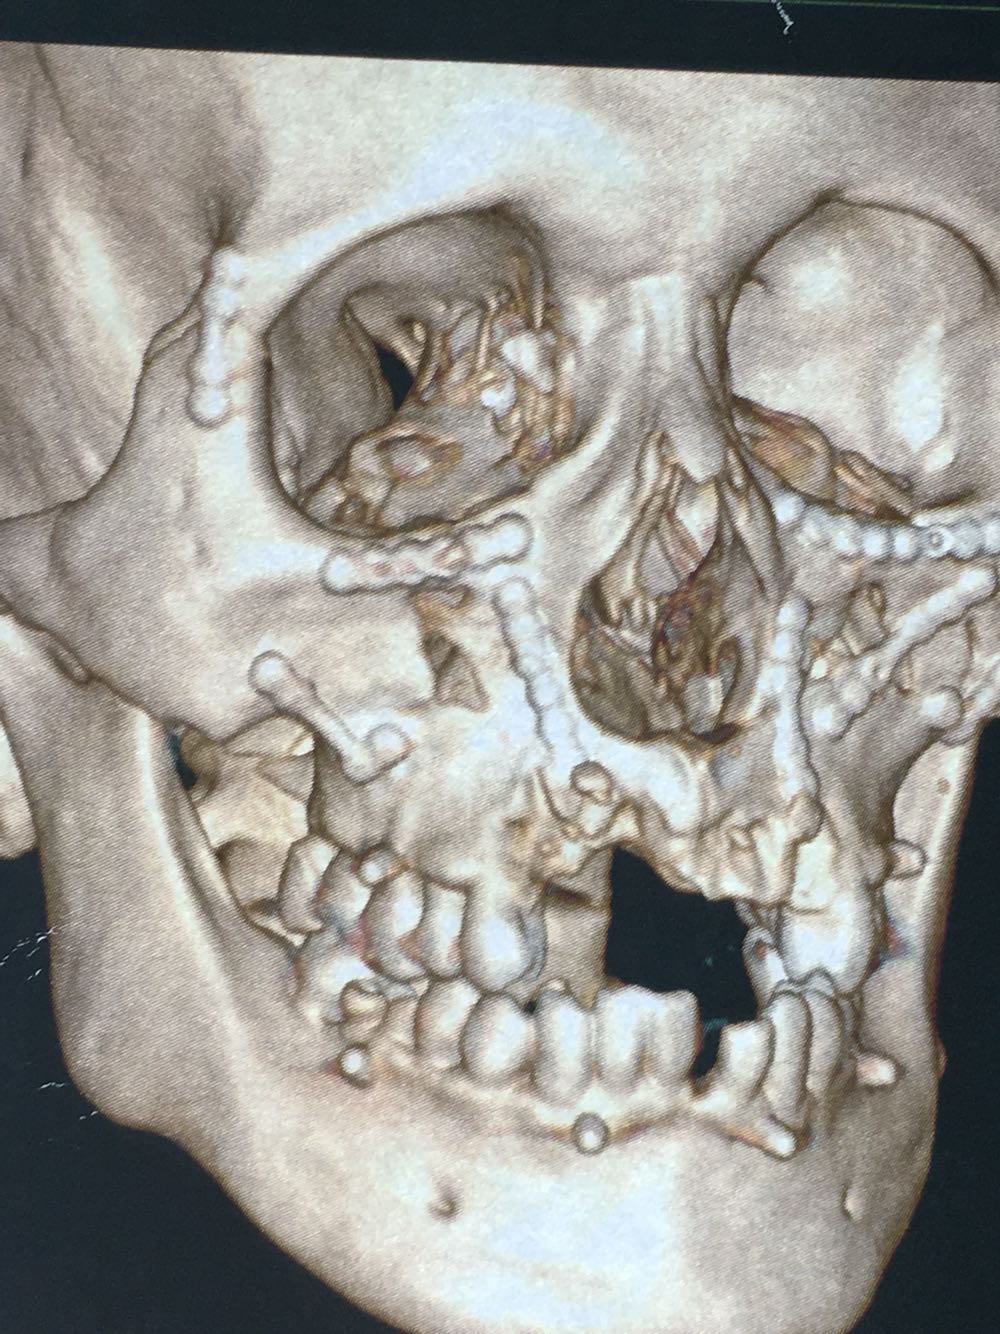

主诉:上颌骨骨折及锁骨骨折术后1年要求拆除内固定装置

治疗:全麻下双侧上颌骨骨折术后留置钛板取出及锁骨骨折术后钢板取出

讨论:颌骨内固定材料现在基本都主张手术取出,这个病人锁骨内固定材料由口腔科医生手术的,有超范围行医行为,最好由骨科完成。